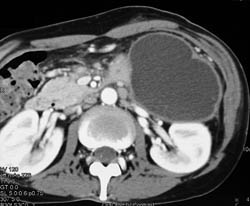

Diagnosis

Intraductal Papillary Mucinous Neoplasm (IPMN)